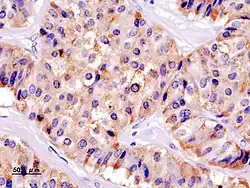

Гистологическая картина

- Патогистология

Панкреатическая инсулинома Окраска инсулиномы Chromogranin A - Histopathology of pancreatic endocrine tumor (insulinoma). Insulin immunostain.